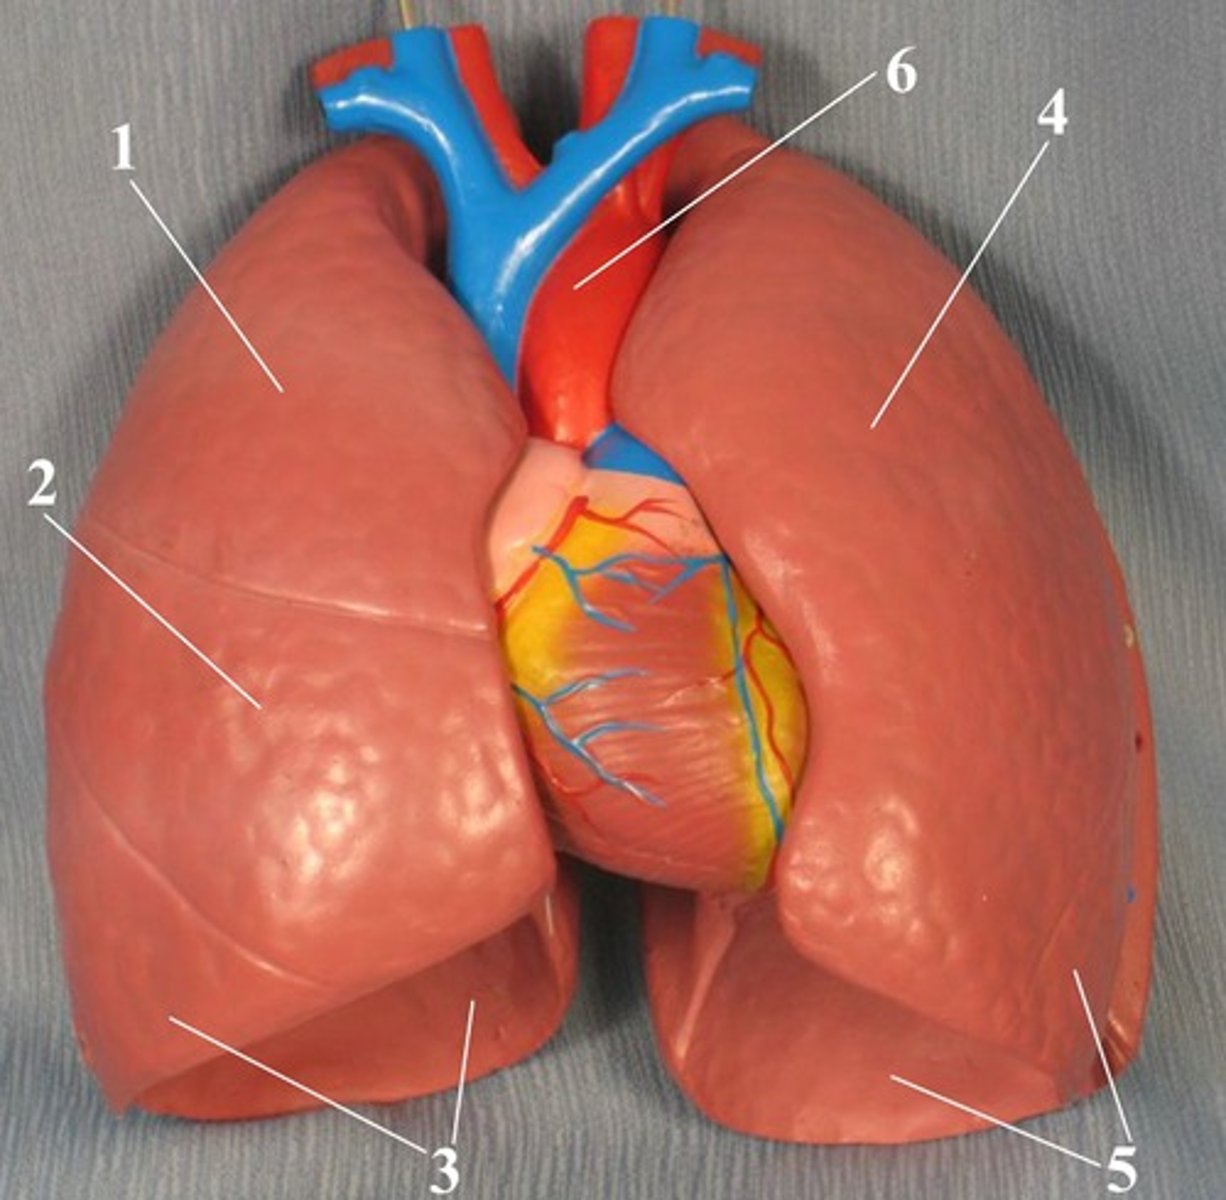

parietal pleura

#2

<p>#2</p>

New cards

visceral pleura

#1

<p>#1</p>

superior lobe of the lung

middle lobe of the right lung

knowt flashcard image

inferior lobe